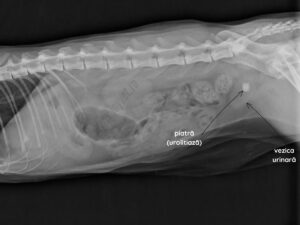

Pietre urinare la câini (calculi urinari)

Ce sunt pietrele urinare și unde se pot forma? Pietrele urinare (numite și calculi urinari [...]